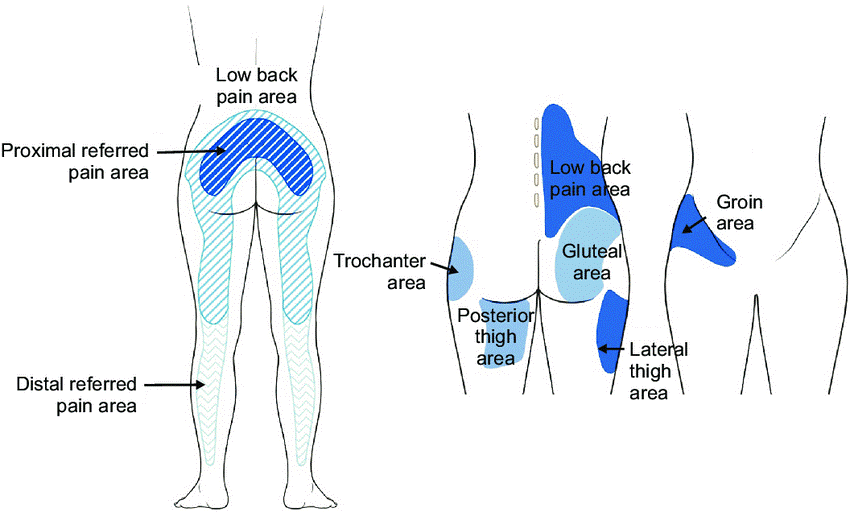

Radiation Pattern of the Pain

While lumbar facet joint pain typically starts in the lower back, it can also radiate to other areas of the body. The radiation pattern of this pain is often more localized than the radiating pain associated with conditions like sciatica. It commonly spreads to the buttocks, thighs, and sometimes the groin. This radiation is usually limited to the same side as the affected facet joint.

Illustration of distribution pattern related to facet joint pain.